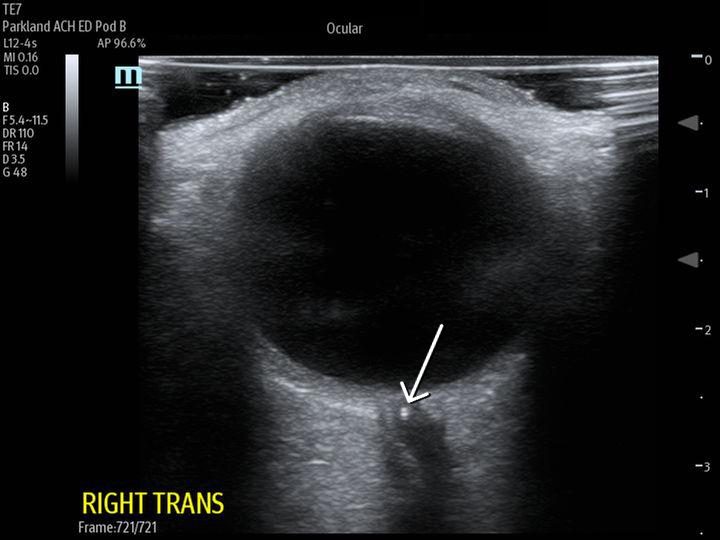

Central retinal artery occlusion (CRAO) is a rare emergency department presentation with high morbidity and potential for long-term vision loss. Additionally, this finding requires an expeditious embolic workup for possible systemic pathology (i.e., stroke). The gold standard for diagnosis is visualization of a pale retina with a "cherry-red spot" on the fovea seen under dilated fundoscopic examination. However, performing a dilated fundoscopic exam is often not practical and technically challenging in the emergency room setting. Alternatively, point of care ultrasound is an inexpensive, non-invasive tool that is already highly utilized in the emergency department and can aid in diagnosis. In the case described in this report, a 66-year-old female presented to the emergency department with painless, monocular vision loss. Ultrasound showed a hyperechoic density on the distal aspect of the optic nerve ("retrobulbar spot sign") and dilated fundoscopic exam showed right eye pale macula with cherry red spot, all consistent with CRAO. Here we present a case that suggests an opportunity for improvement in evaluation of monocular vision loss in the emergency department by adding bedside ocular ultrasound to aid in more rapid diagnosis of CRAO.